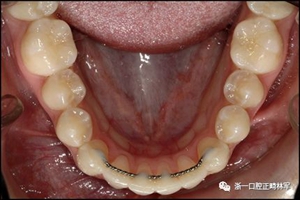

圖9.下頜右側尖牙粘合失敗的柔性螺旋弓絲保持器的咬合面視圖,但是下頜左側尖牙嚴重的舌側傾斜和面?zhèn)雀街鴨适А?/p>

臨床檢查顯示固定保持器完好,弓絲沒有斷裂(圖13)。在下頜右側中切牙唇側和鄰近側切牙的舌側注意到有牙齦退縮。這些牙齒在退縮方向上存在顯著的扭矩差異。下頜的左側尖牙頰側錯位,而右側尖牙舌側傾斜。三維射線照片證實了下頜右側尖牙面?zhèn)妊啦酃菃适?,右側中切牙的喪失程度較輕。右側側切牙根也從舌側骨面上扭轉出來(圖14)。

圖13.粘合到尖牙和切牙上的柔性螺旋弓絲保持器,伴有牙齦退縮和附著喪失,中切牙之間嚴重的扭矩差異以及兩顆尖牙的橫向移動和扭矩。牙周問題和牙齒移動的嚴重程度均為牙周正畸聯(lián)合治療的指征:A,正面視圖; B,咬合面視圖。